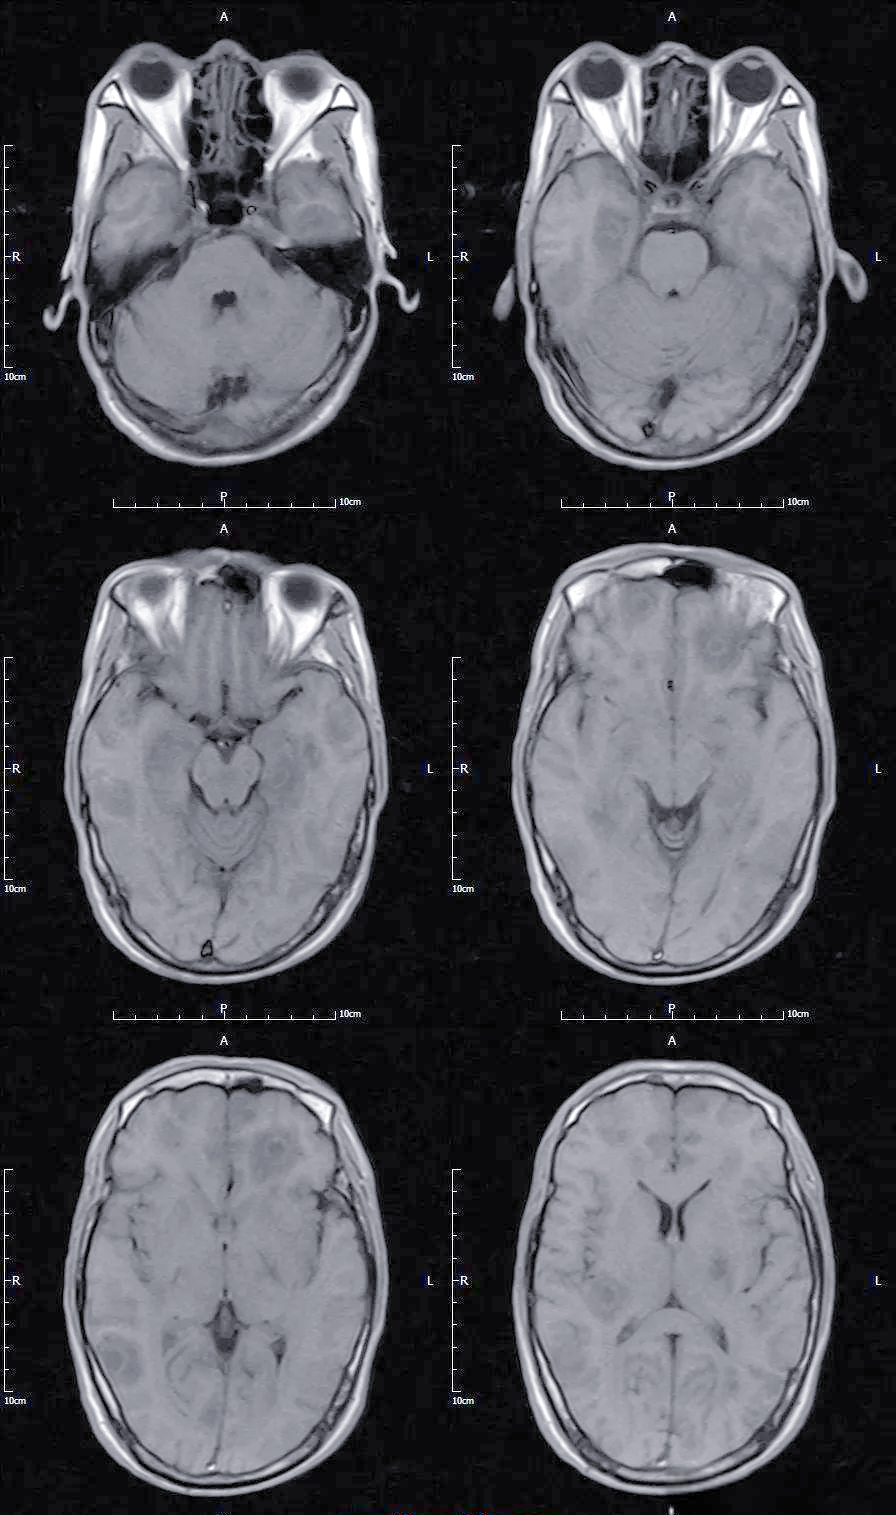

脑囊虫病

术语缩写脑囊虫病(neurocysticercosis,ncc)同义词囊虫病定义由猪肉

囊虫病:一种常见的中枢神经系统寄生虫感染